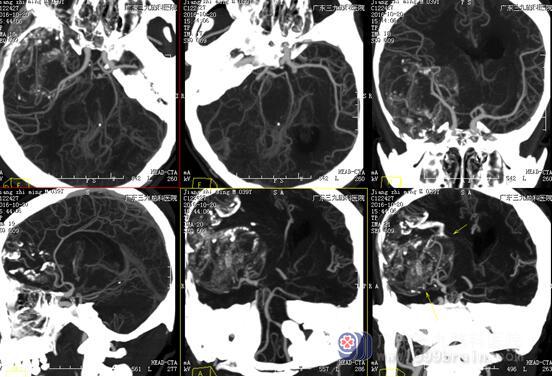

图2:术前CTA检查示:右侧额颞叶巨大高低混杂密度影

少突胶质细胞瘤无包膜,与周围脑组织界限清晰,50%-80%病例出现钙化,可散在或融合成较大的钙化小体,弯曲条带状钙化为其特征性表现,但广泛钙化罕见。本例肿瘤巨大(范围约为10.8×8.6×8.7cm),CT示斑片状低密度影及条带状典型高密度钙化影,病灶内及边缘示多发迂曲血管影沿钙化斑块走行,强化后呈轻度不均匀异常强化影,均符合少突胶质瘤典型影像学改变。